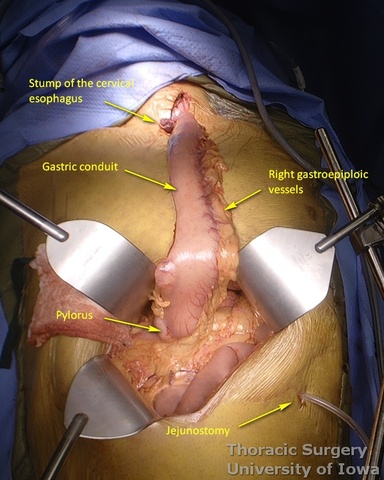

Conduit Preparation and Positioning

- At approximately the level of the third large vein (accompanying vagal “crow’s foot”) along the lesser curvature, lymphatic tissue and vessels are mobilized and divided to expose the gastric wall.

- Starting from the lesser curvature of the stomach, several stapler loads are sequentially fired towards the fundus of the stomach, thus creating a 4–5 cm wide gastric conduit and ensuring a 5 cm margin distal to the tumor. Depending on the thickness of the stomach, medium purple or thick black (alternatively blue or green, depending on manufacturer) loads are used.

- Gastric conduit should reach the cervical incision.

- The gastric conduit stapler line is then oversewn with a running 4-0 (KP and JK) or 3-0 (EA) PDS.

- A Saratoga sump drain (or chest tube) is advanced from the cervical incision through the chest into the abdomen. A Penrose drain is sewn to the anterior wall of the gastric tube (in the area of expected gastrotomy for the anastomosis) and tied over the sump drain.

- The gastric conduit is gently delivered through the mediastinum into the neck without torsion.